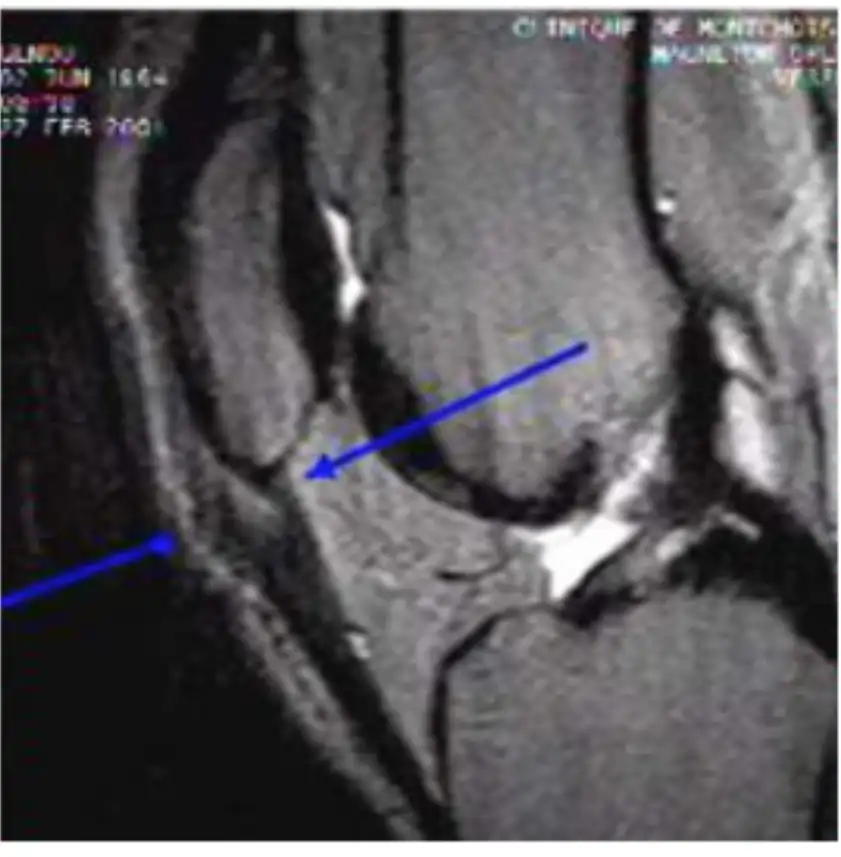

Lesão do Ligamento Cruzado Anterior (LCA) do Joelho

O ligamento cruzado anterior (LCA) é o principal estabilizador do joelho, impedindo o deslocamento anterior da tíbia em relação ao fêmur. Pacientes com lesão do LCA frequentemente relatam um episódio de entorse ou trauma no joelho, seguido de inchaço, dor e, posteriormente, sensação de falseio.

A instabilidade causada por essa lesão pode levar a lesões degenerativas da cartilagem articular a partir de 6 meses. Após 5 anos de lesão, 50% dos pacientes desenvolvem artrose no joelho, e após 10 anos, 75% apresentam esse quadro.

Em 50% dos casos, pacientes com lesão do LCA também possuem lesões meniscais associadas, sendo mandatório investigar essas ocorrências. O exame clínico, com testes como Lachmann e Pivot Shift, possui alta acurácia no diagnóstico.